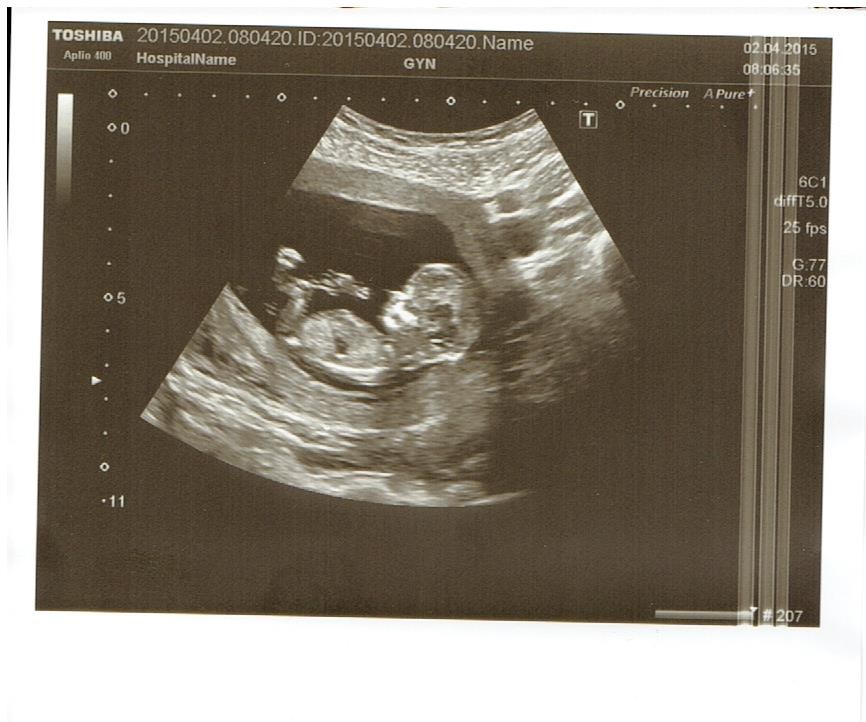

Ahoj maminky a budoucí maminky 😉 Prosím, poradila byste mi některá, co vidíte na fotce z ultrazvuku ve 20. týdnu za pohlaví? Určitě jste foteček viděly už mraky, proto vás žádám o radu...Nechci nikoho ovlivnit, proto svůj tip řeknu později 🙂 Děkuju moc!!!

Do dnešního dne mi můj dr. tvrdil, že je to holka jako vyšitá a dneska na velkém ultrazvuku mi paní doktora řekla kluka - a blejskla tuhle fotku... (na pindíka s varlátkama mi to přijde velký) a i do papírů napsala normální mužský genitál.

@kat_84 jestli je to pohled mezi nožičky zespoda, jak se mi zdá, tak takhle holka opravdu nevypadá. Věřila bych doktorce na velkém uzv, jednak má (při vší úctě ke gynekologovi) podstatně větší zkušenosti a pravděpodobně i lepší přístroj a druhak mě se to proporcionálně nezdá tak mimo, je to hodně zvětšené, vem si, jak obrovská vypadá ta nožička, celé to stehýnko je velké.

Taky bych řekla kluk, je tam pěkně vidět pindík 🙂